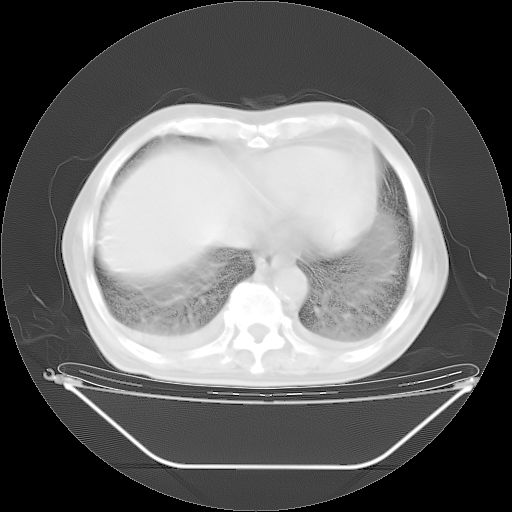

今天复查肺部CT,发现双肺广泛磨玻璃样改变。所以我把3月19日和5月9日相隔50天的肺部CT上传。请大家会诊。

2009年3月19日肺部CT片。

2009年3月19日肺部CT